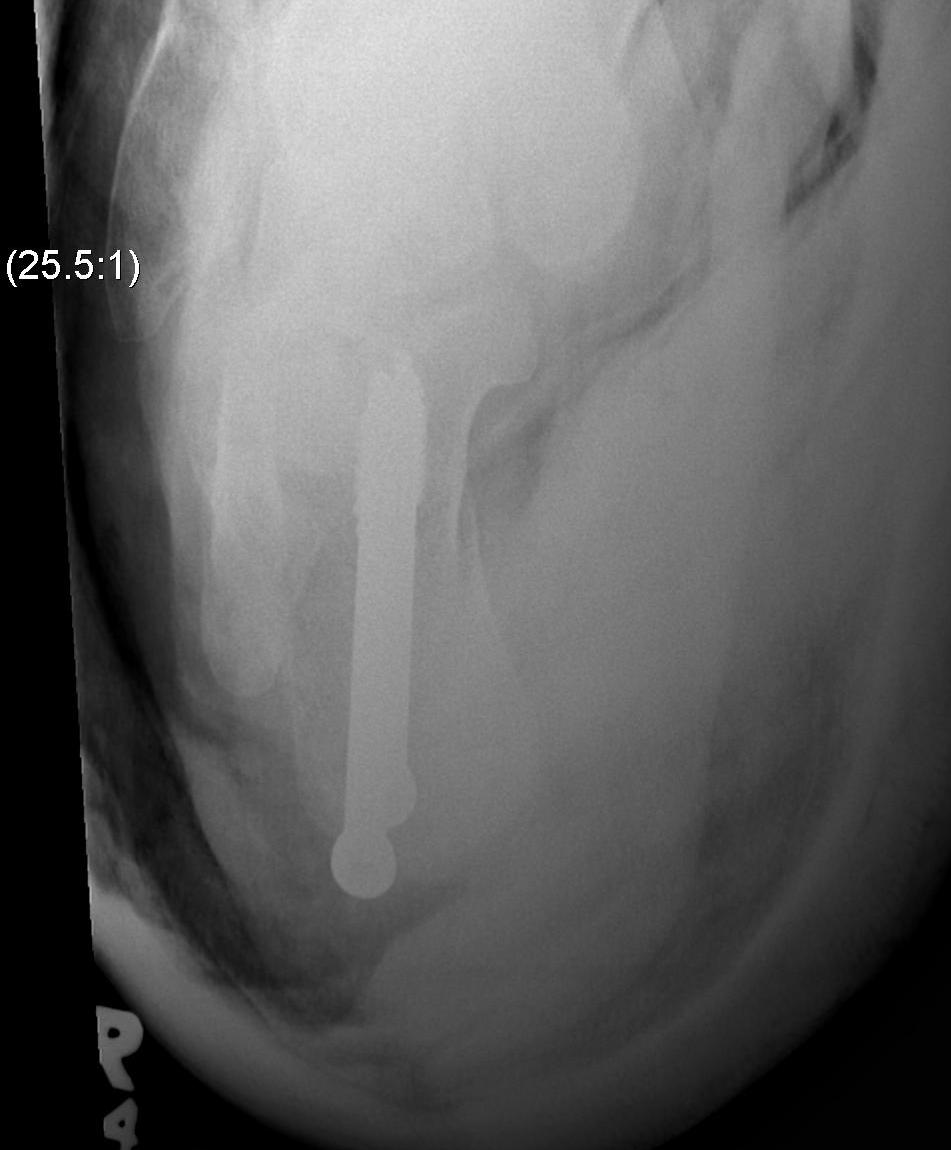

Hindfoot fusion

www.boneschool.com/pantalar-fusion